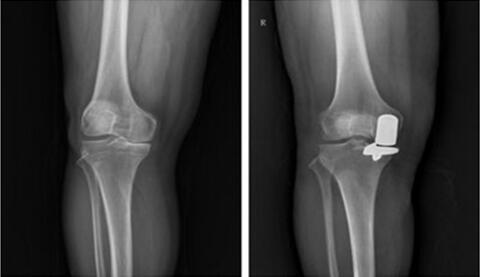

你的膝关节需要 补补牙 吗 青岛市市立医院成功开展膝关节外侧单髁置换术